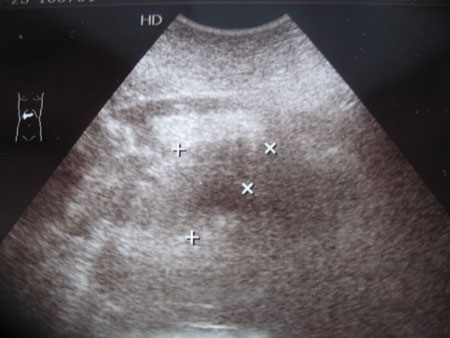

Мужчина П. Приемный покой: жалобы на боли в животе, тошноту

- IMG_6683w.jpg (27.15 КБ) 1949 просмотров

Инга,я например вижу ПЖ с нечёткими контурами,размеры,как мне кажется,увилечены,да и сама она отёчная.Я бы сказала что имеется панкреатит

Размеры увеличены, выраженный отек парапанкреатической клетчатки,

( p.s амилаза 1940) Да, острый панкреатит.

З.Ы.Желательно оставлять сантиметровые отметки на сонограмме. Такой уровень амилазы - в крови или моче? если в моче, то это в пределах нормы.